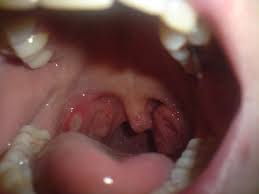

Tiny Bumps On Mouth Roof - Oral Cavity Cancer Johns Hopkins Medicine / In this article, learn what can cause a bump on the roof of the mouth, including possible additional symptoms and when to see a doctor.. Sometimes, bumps on the roof of your mouth can be caused by damaged saliva ducts or smoking. This article will cover the most common causes of a hard bump on the roof of your mouth. A bump can form on the roof of the mouth due to many conditions, including canker sores, mucoceles, torus palatinus, and oral candidiasis. On one ocassion when i wasn't well they became red, but i don't think they are normally like that. Palatal tori are the most common bony growth on the roof of mouth occurring in close to 30 percent of the population.

M having a bit of a sore throat now, when i looked in the mirror, i noticed some very very tiny white spots on the roof of my mouth(not sure if it was there before) and very very tiny bumps on the. Painful bumps on roof of mouth. I get painful bumps on the roof of my mouth when i'm eating sometimes and i push on them and they go away. They can be a reason for great concern for those who experience it. They appear little white or yellow bumps on gums and roof of mouth.

Should i be worried if the roof of my mouth is itching? Mouth can be very much complicated especially when it comes to the issues to do with the hard palate. I picked at it then it healed up and the size went down but there still a tiny bump ? Strange bumps on mouth roof mouth may appear in different forms, shapes, color, and distribution. Bump on roof of mouth that randomly appeared with a little pain. Is the tiny lump a different color to the rest of your mouth? Your abscess on the roof of your mouth or palatal abscess typically represents the directed drainage coming from an infection of your tooth nerve or how much ciggretes can cause mouth cancer? It will start small and grow significantly larger if you dont have it surgically removed. This article will cover the most common causes of a hard bump on the roof of your mouth. A bump on roof of mouth that has been around for a long time may point to oral cancer. Therefore, this is something that can easily be small bumps in the mouth are caused by many things. In the roof of the mouth toward the anterior there is sometimes a series of ridge formed by the mucosal folds, these are called ruggae. When you state tiny, roughly what size would you say it was in millimetres?

A bump on the roof of mouth can mean oral cancer, ulcers, some stds, allergies, canker sores etc. Bumps in mouth may result from food irritation, canker sore, mucous cysts and other health these bumps will appear on the inner surface of your lips and don't usually affect the roof or floor of the if large white patches form on your tongue as well as the roof of your mouth because this could be due. The incisive papilla is a small oval shaped or pear shaped projection of the. Bumps and ulcers that appear on the roof of the mouth are not uncommon. If you felt a bump, then you're part of a small percentage of the population who has one.